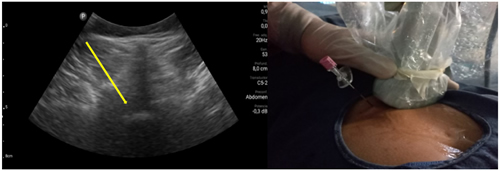

Pacientes y métodos: Un total de 25 pacientes con dolor radicular lumbosacro fueron seleccionados para recibir inyecciones epidurales interlaminares de esteroides en posición decúbito dorsal, utilizando la técnica ecoguiada en plano, en tiempo real, en eje corto o transversal. En todos los casos, un epidurograma de control fue realizado previo a la inyección de la solución de esteroides. El rendimiento de la técnica fue estudiado mediante la tasa de éxito de la misma, entendido como éxito a la obtención de un epidurograma sin necesidad de abandonar la técnica ecográfica en un tiempo menor a 10 minutos. El rendimiento del procedimiento fue estadísticamente evaluado por el método de la suma acumulativa (CUSUM), y la curva de aprendizaje aplicando este método fue construida.

Resultados: La distancia promedio desde la piel al complejo posterior evaluada por el escaneo ecográfico previo al procedimiento fue de 6,7 ± 1,8 cm. De los 25 procedimientos realizados, en 21 se alcanzó el espacio epidural sin ayuda de la fluoroscopia, en un tiempo promedio de 4,8 ± 1,2 minutos. Esto constituye una tasa de éxito del 84 %. En los cuatro procedimientos restantes el espacio epidural fue alcanzado con éxito mediante el uso complementario de la fluoroscopia.

Figura 2